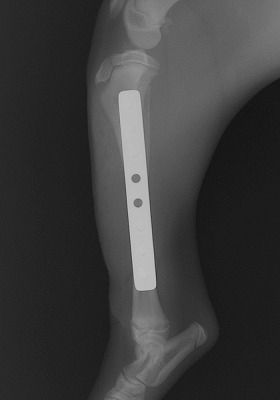

手術をして元の状態に骨を整復しました。

Img5979-1.jpg